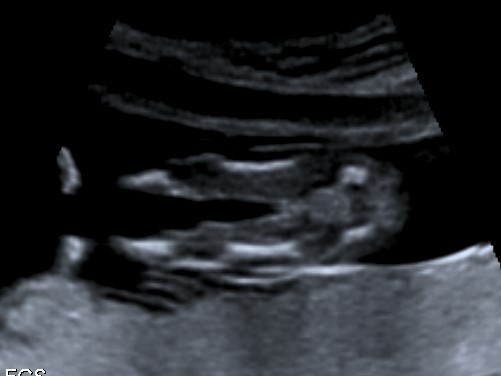

No good nub shots though. This is bubs skull, potty shot (though baby was 12&1 at my scan but measuring ahead at 13wks, so I think its way too early) and a side profile. Would love some educated guesses.